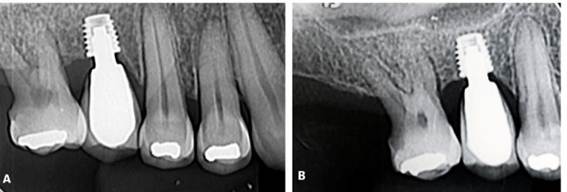

Paciente A. R. S, gênero feminino, 67 anos de idade, compareceu ao consultório particular, em 2020, com a queixa de mobilidade na região dos implantes inferiores. Na anamnese, paciente realizava acompanhamento médico devido ao quadro de diabetes mellitus, com uso de medicamentos específicos. Ao exame clínico, verificado mobilidade acentuada na regão do 36, 37, 46 e 47. Foram solicitados radiografia panorâmica (Figura 04. A) e tomografia computadorizada da área, evidenciando comprometimento periodontal avançado nas reabilitações com implantes dentários. O plano de tratamento proposto foi a remoção dos implantes e nova reabilitação da região atrófica.

Inicialmente, o procedimento cirúrgico consistiu pela remoção dos implantes dentários (Figura 04. B), realização de enxerto imediato (Bio-Oss, Geistlinch, Wolhusen – Suíça), através da técnica de reconstrução tipo tenda, e uso da membrana de colágeno (Bio-Gide, Geistlinch, Wolhusen – Suíça). O Quadro 1 apresenta as principais medidas para avaliação do posicionamento do implante. Após 6 meses, foram instalados dois implantes dentários extra curtos ARCSYS (FGM, Joinvile – SC, Brasil) 4,0 mm x 6,0 mm x 5,0 mm do lado direito e dois implantes na região esquerda 5,0 mm x 5,0 mm. As figuras 05 e 06 evidenciam aspecto radiográfico após a etapa inicial. As recomendações pós-operatórias e a prescrição medicamentosa foram realizadas, resultando em ausência de complicações após a intervenção. O acompanhamento foi feito durante 5 anos, com resultado satisfatório (Figura 7. A – E).

Figura 04. A) Radiografia panorâmica inicial. B) Implantes dentários removidos – região do 36, 37, 46 e 47.

Figura 05. Exames de imagem da região inferior direita. A) Vista panorâmica. B) Reconstruções tridimensionais. C) Cortes transversais oblíquos.

Figura 06. Exames de imagem da região inferior esquerda. A) Vista panorâmica. B) Reconstruções tridimensionais. C) Cortes transversais oblíquos.